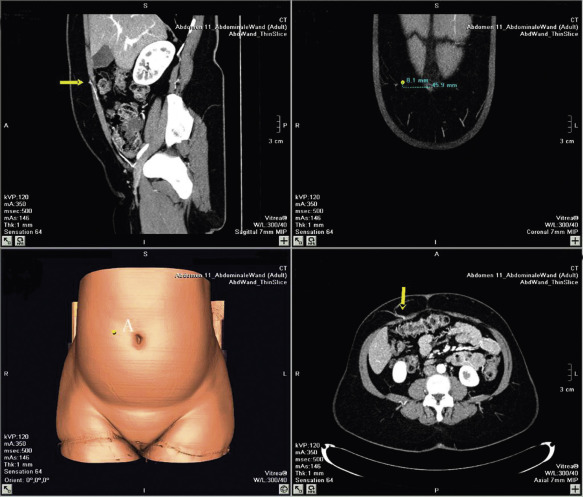

The preoperative investigation should include a study of the abdominal wall vascular anatomy. Although it is possible to harvest a DIEAP flap without prior knowledge of the exact position and size of the perforators, we believe it is much safer and faster to do so with a map of the perforators on hand. Therefore, angio-CT imaging is used routinely in our department in the planning of DIEAP flaps. This allows the creation of a 3-dimensional map of the perforating vessels with coordinates centered on the umbilicus. An alternative to angio-CT, duplex-Doppler ultrasound allows the location and diameter of the vessels to be evaluated plus the blood flow and arborization patterns. This provides the surgeon with invaluable information to help with the safe planning of a DIEAP flap in different individuals.

The status of the internal mammary vessels is also assessed at the same time, as this is our preferred recipient vessel in breast reconstruction. Alternatively, the perforator mapping can be done using a handheld Doppler; however, one should be aware that, although more accessible and less costly, this device generates more false-positive and false-negative signals and provides less detailed anatomic and functional vessel information.

The use of high-resolution multidetector spiral CT scan has replaced color duplex imaging in our practice. Contrast-enhanced CT scanning appears to be the modality of choice in preoperative investigation of perforating vessels. Although no flow information is obtained, it allows excellent three-dimensional understanding of the arterial and venous perforator morphology and the intramuscular course of the DIEA, DIEV and SEIV ( Fig. 57.5 ). A preoperative angio-CT can gain 60–90 min of operating time. More recently, the use of magnetic resonance angiography has been described for preoperative work-up of perforator vessels. Although great imaging can be obtained with this modality, routine use can be restricted because of accessibility reasons, cost and length of the procedure.